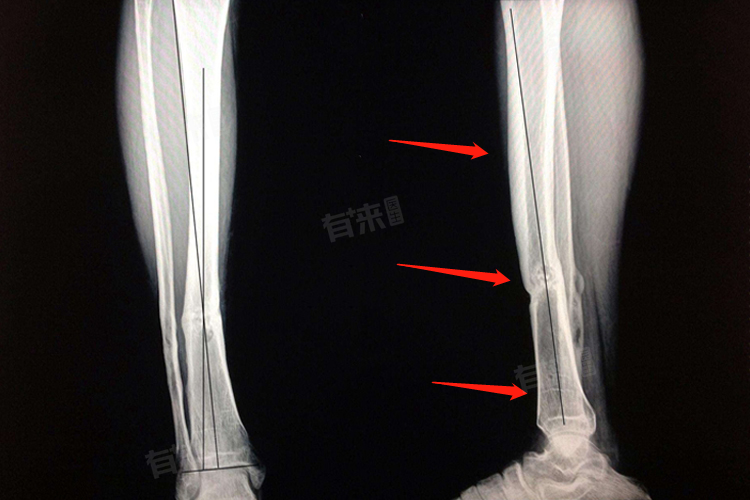

- 对于粉碎性骨折或移位明显的骨折,由于其治疗难度较大,恢复时间相对较长。这类患者往往需要进行切开复位内固定术,术后需躺卧3个月左右,甚至更久。术后康复期间,患者需在医生指导下进行系统的康复训练,包括直腿抬高、踝关节及膝关节的被动活动等,以预防肌肉萎缩、关节僵硬等并发症的发生。